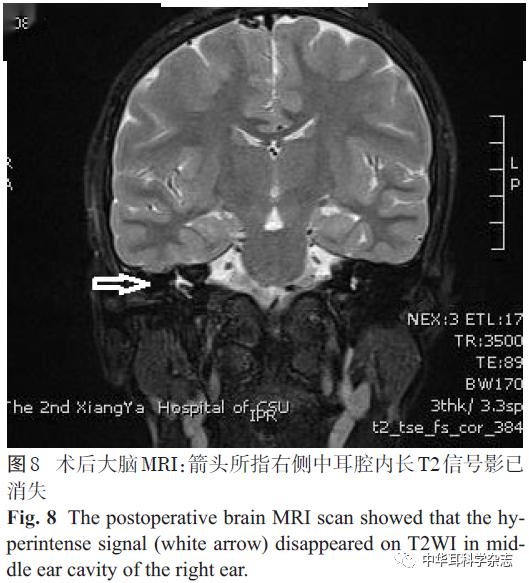

儿童脑脊液耳漏修补与人工耳蜗植入同期手术的探讨

图片尺寸533x351